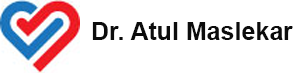

Acute Aortic Dissection. True & False Lumen Flaps seen